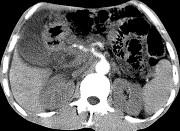

问题 女,50岁,中上腹疼痛,消瘦乏力,影像检查如下图,最佳的诊断是 ( )

选项 A.慢性胰腺炎 B.急性胰腺炎 C.胰腺癌并腹膜后淋巴结转移 D.胰岛素瘤 E.腹膜后淋巴瘤

答案 C